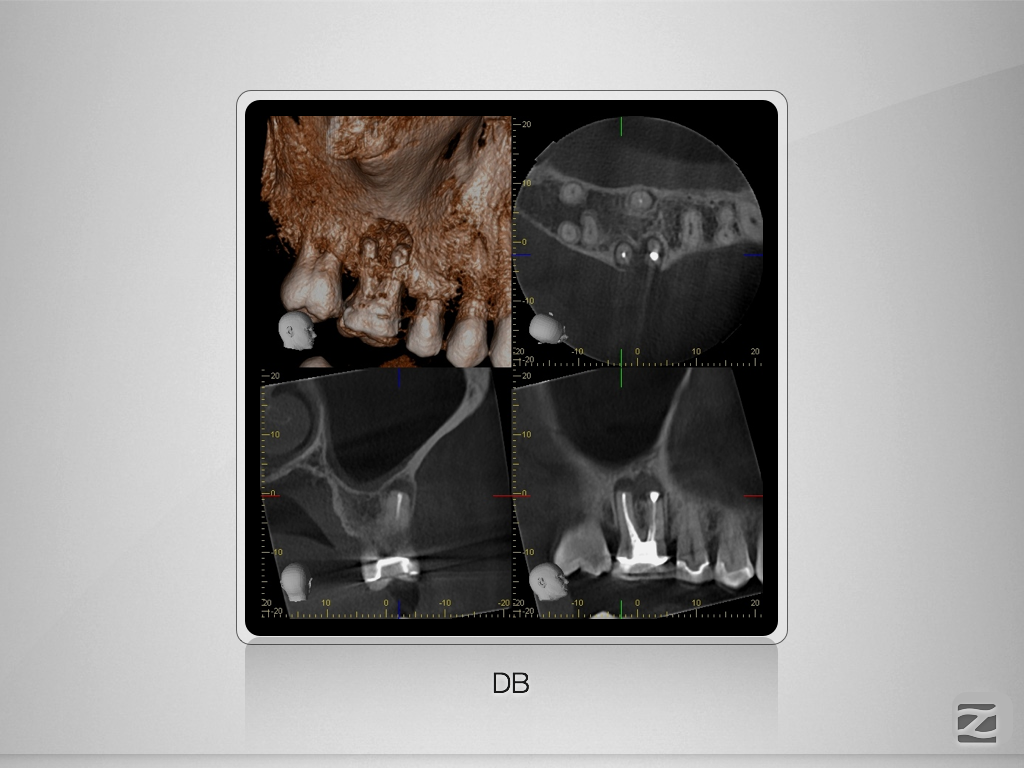

16D.005

1024 × 768

X-Bein/H-förmiger Isthmus/tiefer Split